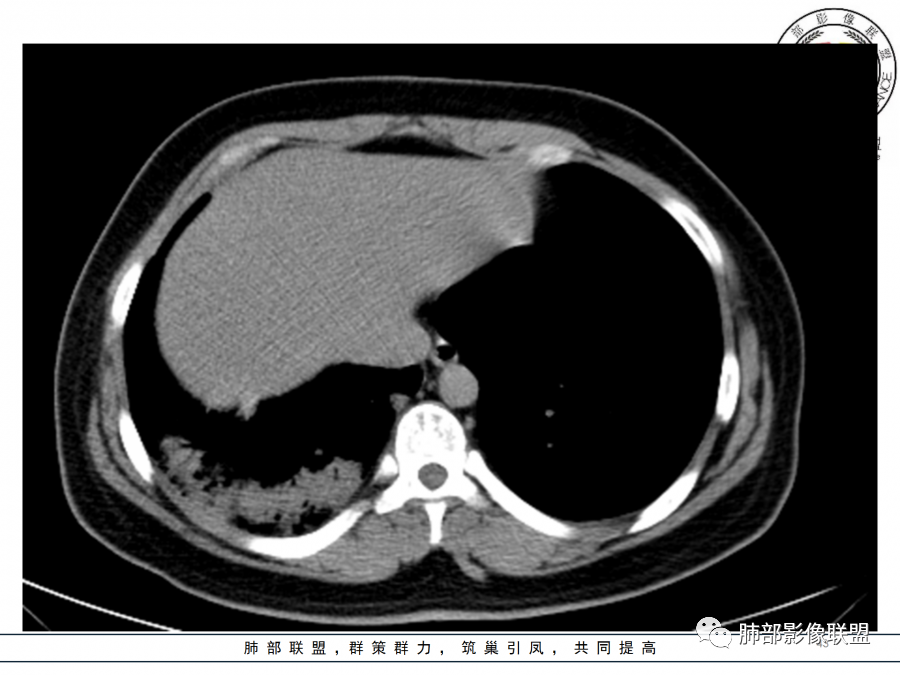

26岁,女性,发热、咳嗽5天。咳少量黄痰,起病急,病程短,白细胞及中性高,血沉及D-二聚体增高。胸部CT:右肺下叶大片实变,长轴沿胸膜分布,宽基底与胸膜接触,边界不清,周围GGO,部分团片影融合,病灶内可见支气管充气征,部分支气管进入病灶后阻塞。考虑:感染性病变,隐球菌?脓毒肺栓塞?鉴别:肺炎型肺Ca。

年轻女性,急性病史,发热,WBC17.42*10^9/L,NE%82.8%,

痰革兰染色示:G-杆菌1+、G+球菌1+,未检出真菌,抗酸染色阴性。

大片实变影

细菌性感染?隐球菌?结核?梗死?

淋巴瘤?肺炎型肺癌?支原体?病毒?

1.年轻女性,咳嗽、发热(38.8°),起病急,血象高。影像上大片实变影为主,一般会首先考虑细菌性肺炎,尤其是肺炎链球菌感染等。疗效不满意时考虑其他。

2.影像上怀疑其他病灶的理由有:

1)实变影为大小不等多中心性。

2)沿胸膜下分布趋势(不同于大叶性肺炎的肺叶“造型”)。

3)周围较大范围磨玻璃影及小叶间隔增厚。

4)病灶体积增大明显(叶间裂推移)。

3.腺病毒肺炎可以符合上述改变:实性密度,间质分布为主等。

4.隐球菌感染可以符合上述改变:胸膜下多中心实变密度为主,磨玻璃晕等。但隐球菌临床症状大多隐匿、迁延,影像变化缓慢。

5.本例患者血象高,影像渗出明显,尚不能排除混合感染可能。